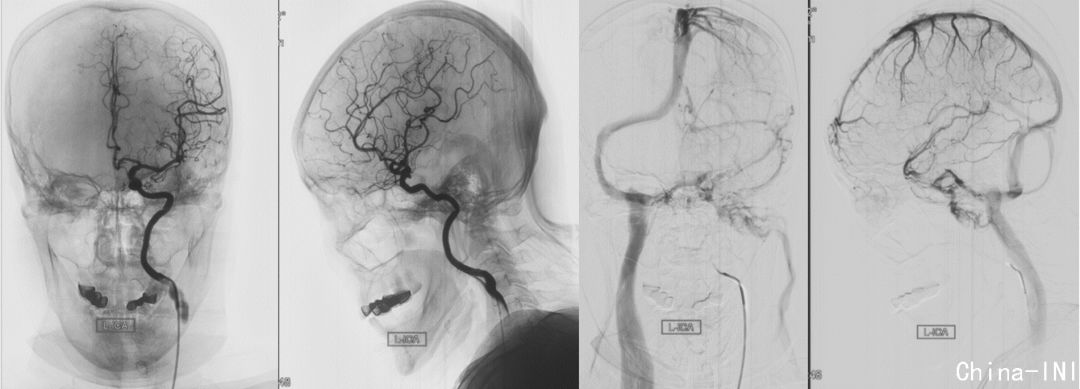

左侧颈内动脉造影,显示左侧颈段颈内动脉受压向前移位,肿瘤无明显血供;左侧乙状窦、颈静脉球及颈内静脉都未显影。肿瘤有无血供及其程度有助于鉴别神经鞘瘤、脑膜瘤及颈静脉球瘤。